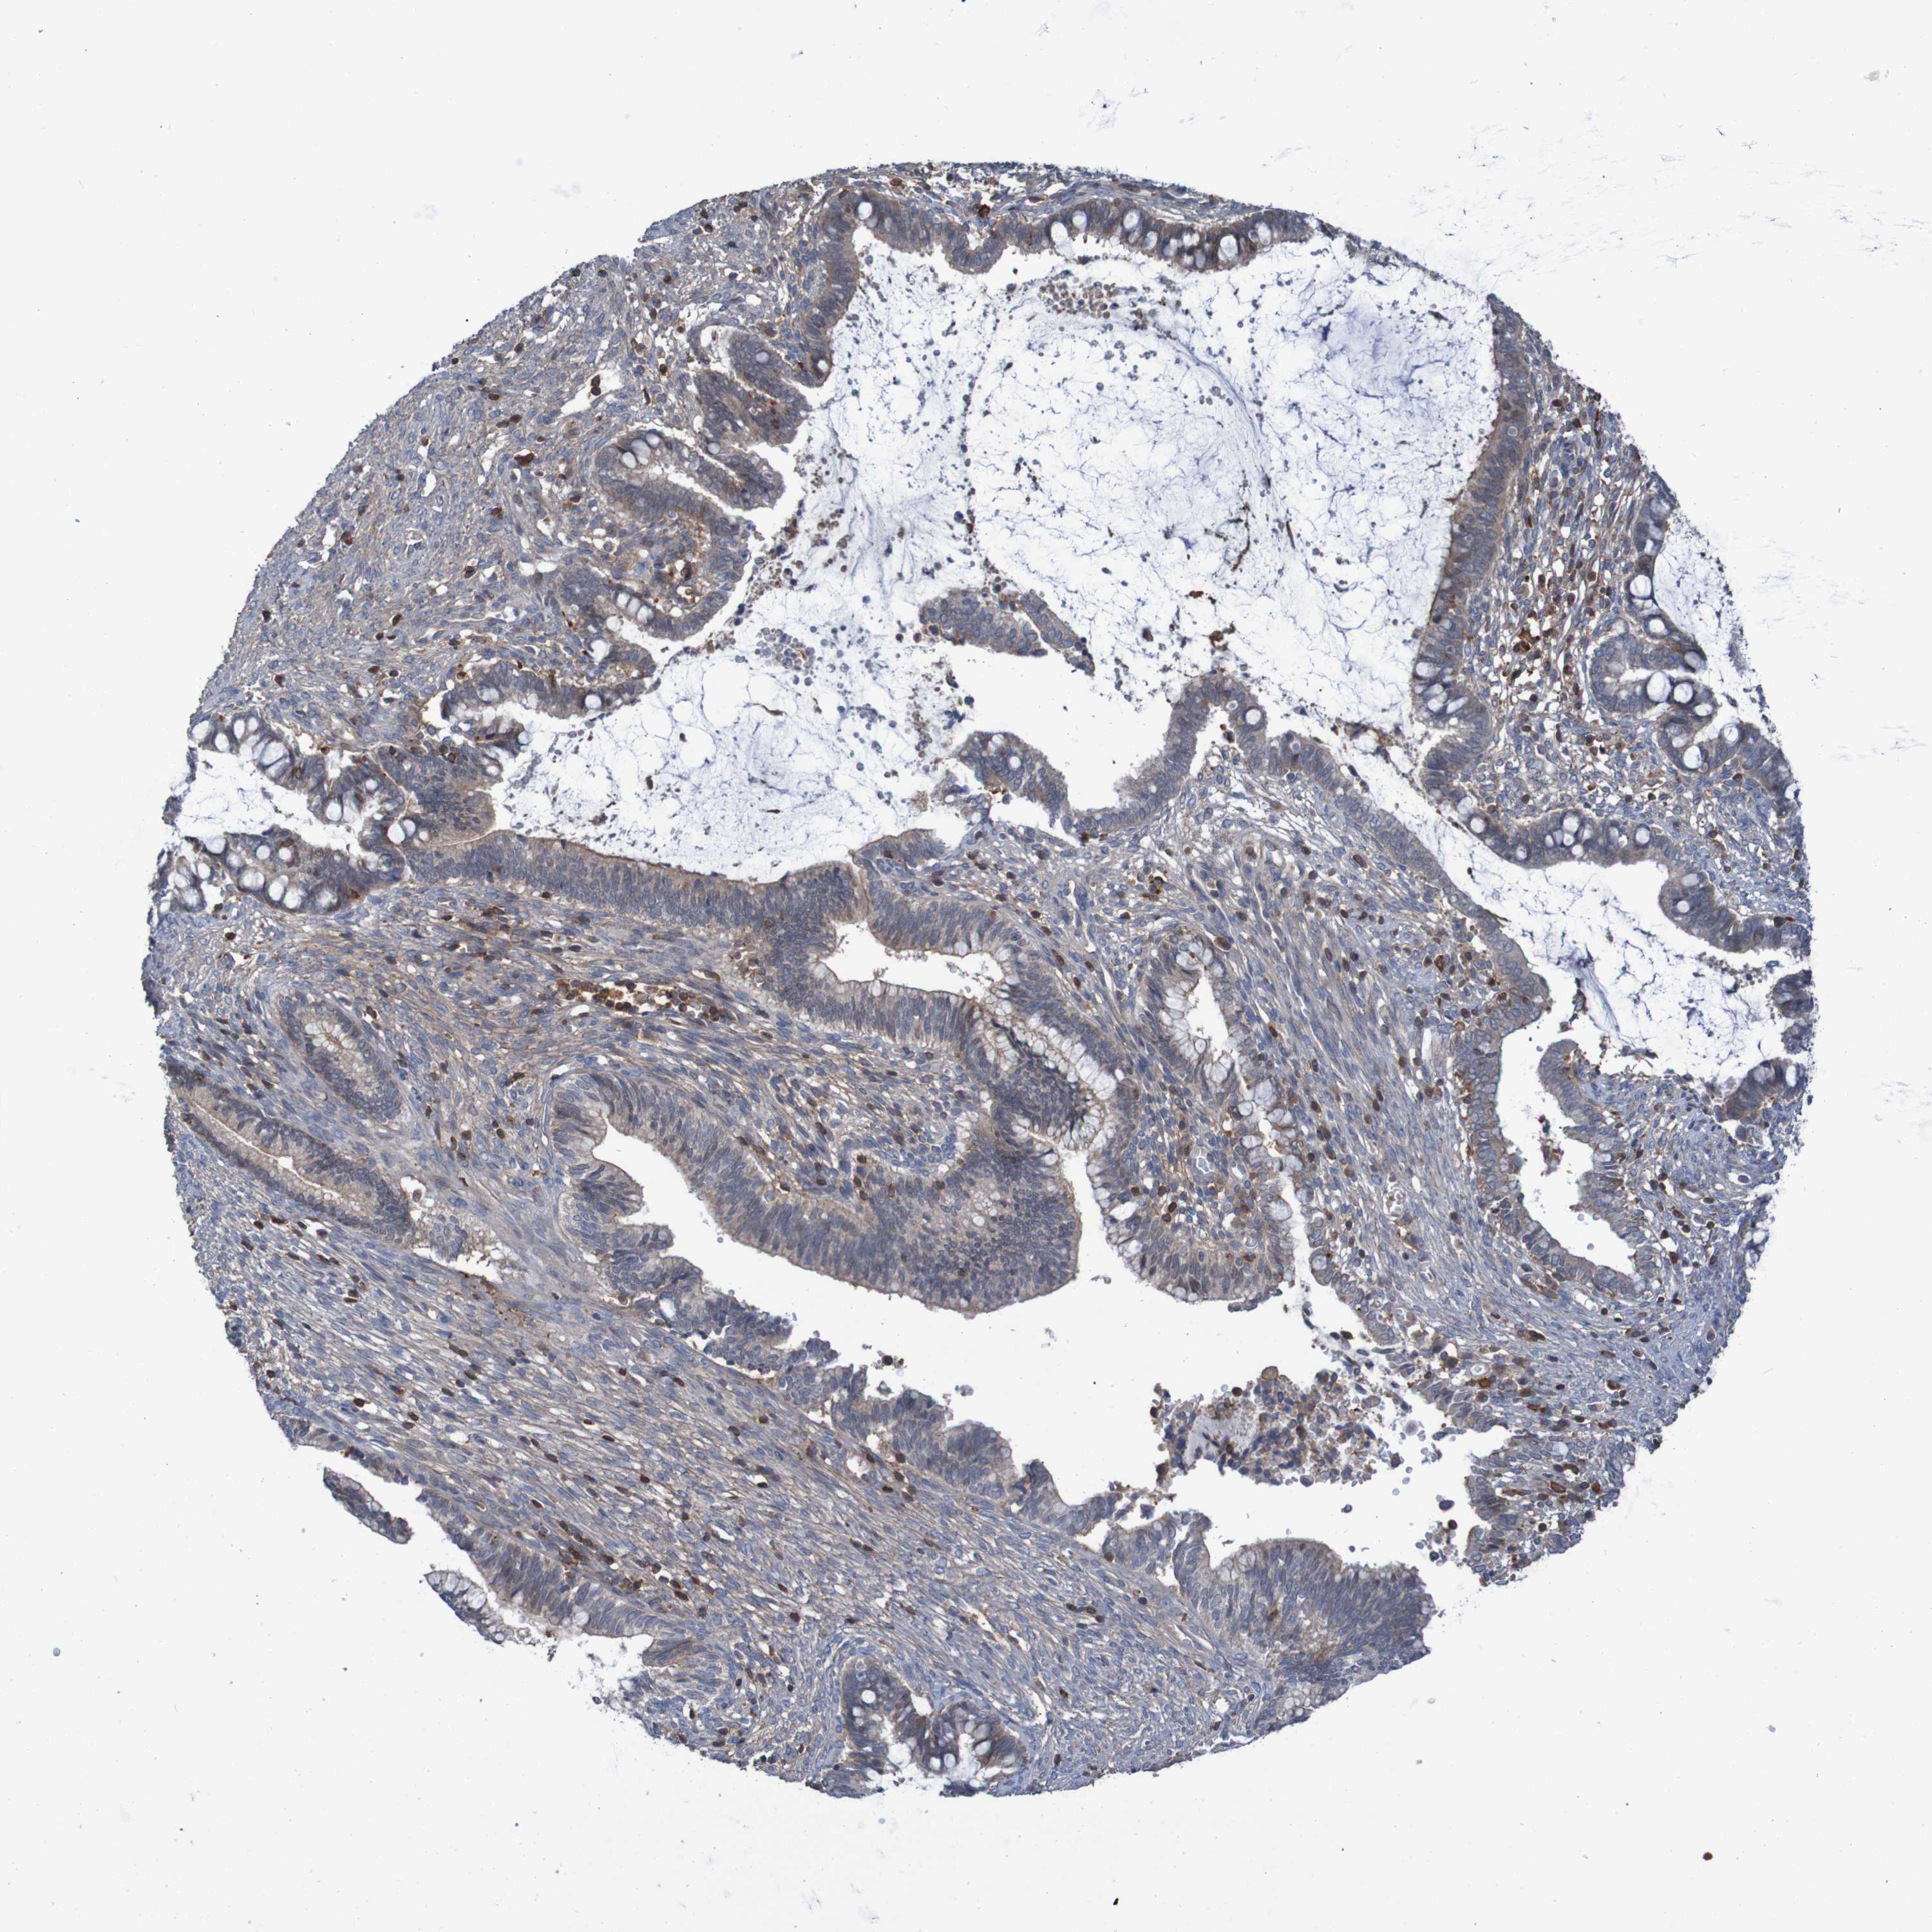

CERVICAL CANCER - Protein expressioni

A mouse-over function shows sample information and annotation data. Click on an image to view it in a full screen mode. Samples can be filtered based on level of antibody staining by selecting one or several of the following categories: high, medium, low and not detected. The assay and annotation is described here.

Note that samples used for immunohistochemistry by the Human Protein Atlas do not correspond to samples in the TCGA dataset.

Antibody stainingi

Antibody staining in the annotated cell types in the current human tissue is reported as not detected, low, medium, or high, based on conventional immunohistochemistry profiling in selected tissues. This score is based on the combination of the staining intensity and fraction of stained cells.

Each image is clickable and will lead to virtual microscopy that enables deeper exploration of all samples and also displays staining intensity scores, fraction scores and subcellular localization as well as patient and tissue information for each sample.

Antibody HPA011972

Antibody CAB011604

Antibody CAB018341

Staining

High

Medium

Low

Not detected

Intensity

Strong

Moderate

Weak

Negative

Quantity

>75%

75%-25%

<25%

None

Location

Nuclear

Cytoplasmic/membranous

Cytoplasmic/membranous,nuclear

Squamous cell carcinoma, NOS

Adenocarcinoma, NOS